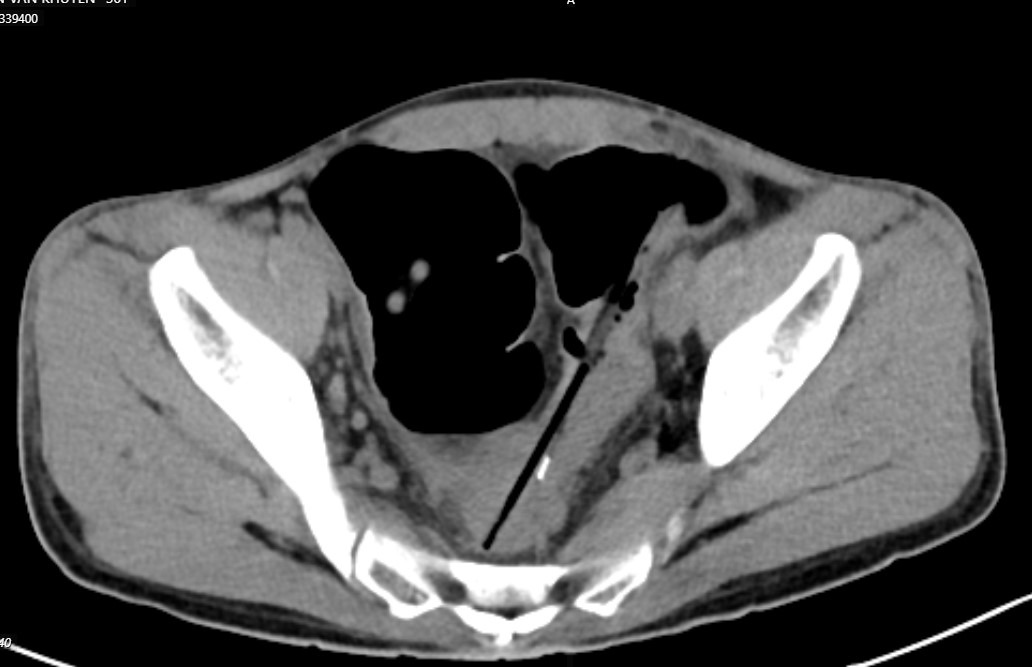

Chụp cắt lớp ổ bụng thấy hình ảnh 2 dị vật hình que đầu kim loại trong quai ruột vùng hạ vị, đâm xuyên thành ruột tạo ổ dịch khí vùng tiểu khung cạnh cơ bịt phải; Dị vật trong quai ruột hạ sườn phải; Dày thành trực tràng, đại tràng sigma và quai ruột ngang rốn; Giãn lan tỏa các quai ruột non.

Bệnh nhân được chẩn đoán: Áp xe trong ổ bụng do thủng đại tràng sigma do dị vật, dị vật ruột non/ tâm thần phân liệt

Hình ảnh chiếu chụp cho thấy nhiều dị vật trong bụng bệnh nhân. Ảnh BVCC